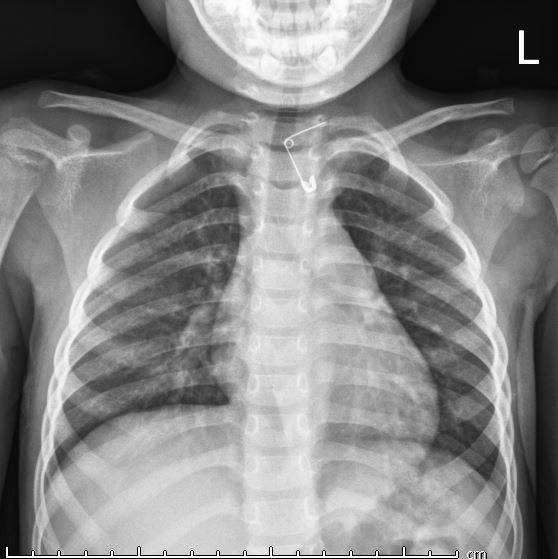

Bệnh viện Sản nhi Quảng Ninh cho biết, sau khi khám lâm sàng, các bác sĩ phát hiện bé V.T. N., 4 tuổi, sống ở Cẩm Phả, Quảng Ninh có dị vật là 1 chiếc kim băng đang mở, một đầu nhọn cắm vào thành thực quản của bé.

Phim chụp X-quang ccủa bé gái. Ảnh: BVCC